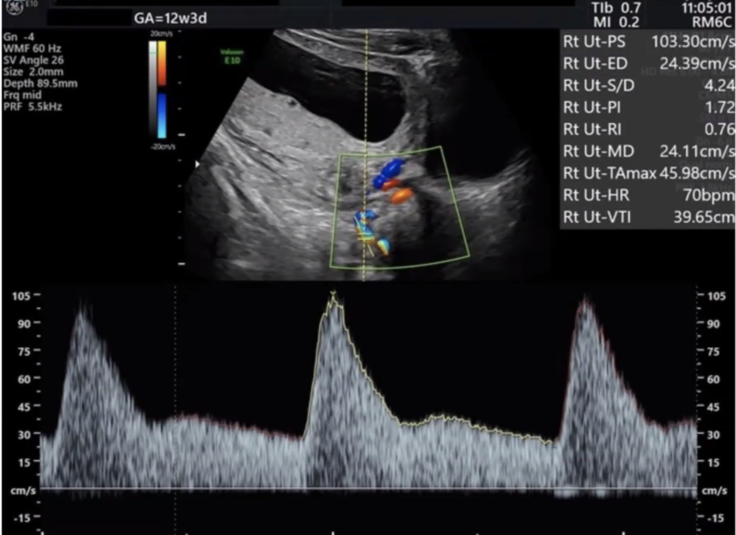

妊婦さんの『血液』と『両腕の血圧測定』、そして『子宮の血流』を超音波で測定し、発症の可能性を確率で知ることができる検査です。妊婦さんも赤ちゃんも痛みのない安全な検査です。年齢や症状のあるなしに関わらず、妊娠11週〜13週であれば、どなたでも受けることができます。

▲子宮動脈を計測した超音波データ

このようなデータをFMFに送って、技術がレベルに達しているか判定されます。